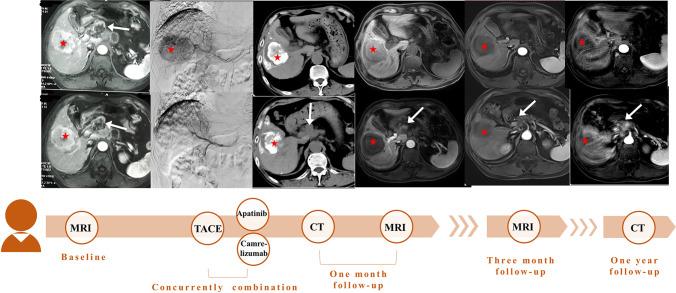

This study aimed to investigate the efficacy and safety of transarterial chemoembolization (TACE) plus camrelizumab, a monoclonal antibody targeting programmed death-1, and apatinib for patients with intermediate and advanced hepatocellular carcinoma (HCC) in a real-world setting.

TACE plus camrelizumab and apatinib showed significantly better OS, PFS, and ORR versus TACE monotherapy for predominantly advanced HCC.

Compared with TACE monotherapy, TACE plus immunotherapy and molecular targeted therapy showed better clinical efficacy for predominantly advanced HCC patients, with a higher incidence of adverse events.